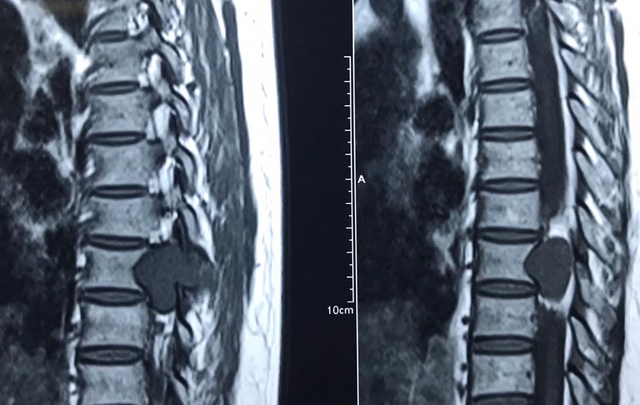

Cách tốt nhất để phát hiện bệnh đó là chụp Xquang hoặc MRI để xác định. Vì bệnh lý này cũng có nhiều đặc điểm giống với bệnh xương khớp khác.

Tôi chụp CHT kết luận thoái hoá đĩa đệm, phình C 4/4 4/5 5/6 gây hẹp ống sống độ , chèn ép rễ C5 hai bê, tại ngách C 3/4. Thoái hoá Modic hai bờ trên thân đốt sống C5. Hiện tại đau không ngoái cổ được khó làm việc! Xin bác sĩ chỉ cách chữa trị!

Tôi đi chụp CHT két quả: phồng lan toả đĩa đệm c5,c6 gây chèn ép bao màng cứng làm hẹp ống sống( DK trước sau 8mm) kèm theo thoái hoá gai xương , mỏm moc làm hẹp lỗ tiếp hợp, chèn ép rễ c6 hai bên. Phồng đĩa đệm c6,7 gây chèn ép bao màng cứng làm hẹp ống sống( DK trước sau 9mm) ko gây chèn ép rõ rệt các dễ thần kinh . Xin bsy tiw vấn. Tôi xin cảm ơn